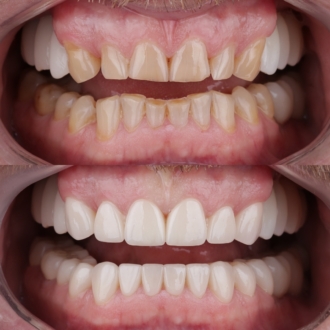

Произведена комплексная эстетическая реабилитация улыбки. Восстановлены правильные пропорции зубов, улучшено цвет и форму, гармонизирована улыбка с чертами лица. Сохранен максимальный объем собственных тканей — достигнут естественный и гармоничный результат.

Произведено: диагностику, цифровую планировку улыбки, моделирование формы зубов, минимально инвазивную подготовку, установку керамических реставраций E-max. Результат: гармоничная форма зубов, естественный цвет и прозрачность, правильная длина резцов, более открытая и выразительная улыбка с сохранением собственных тканей зуба.